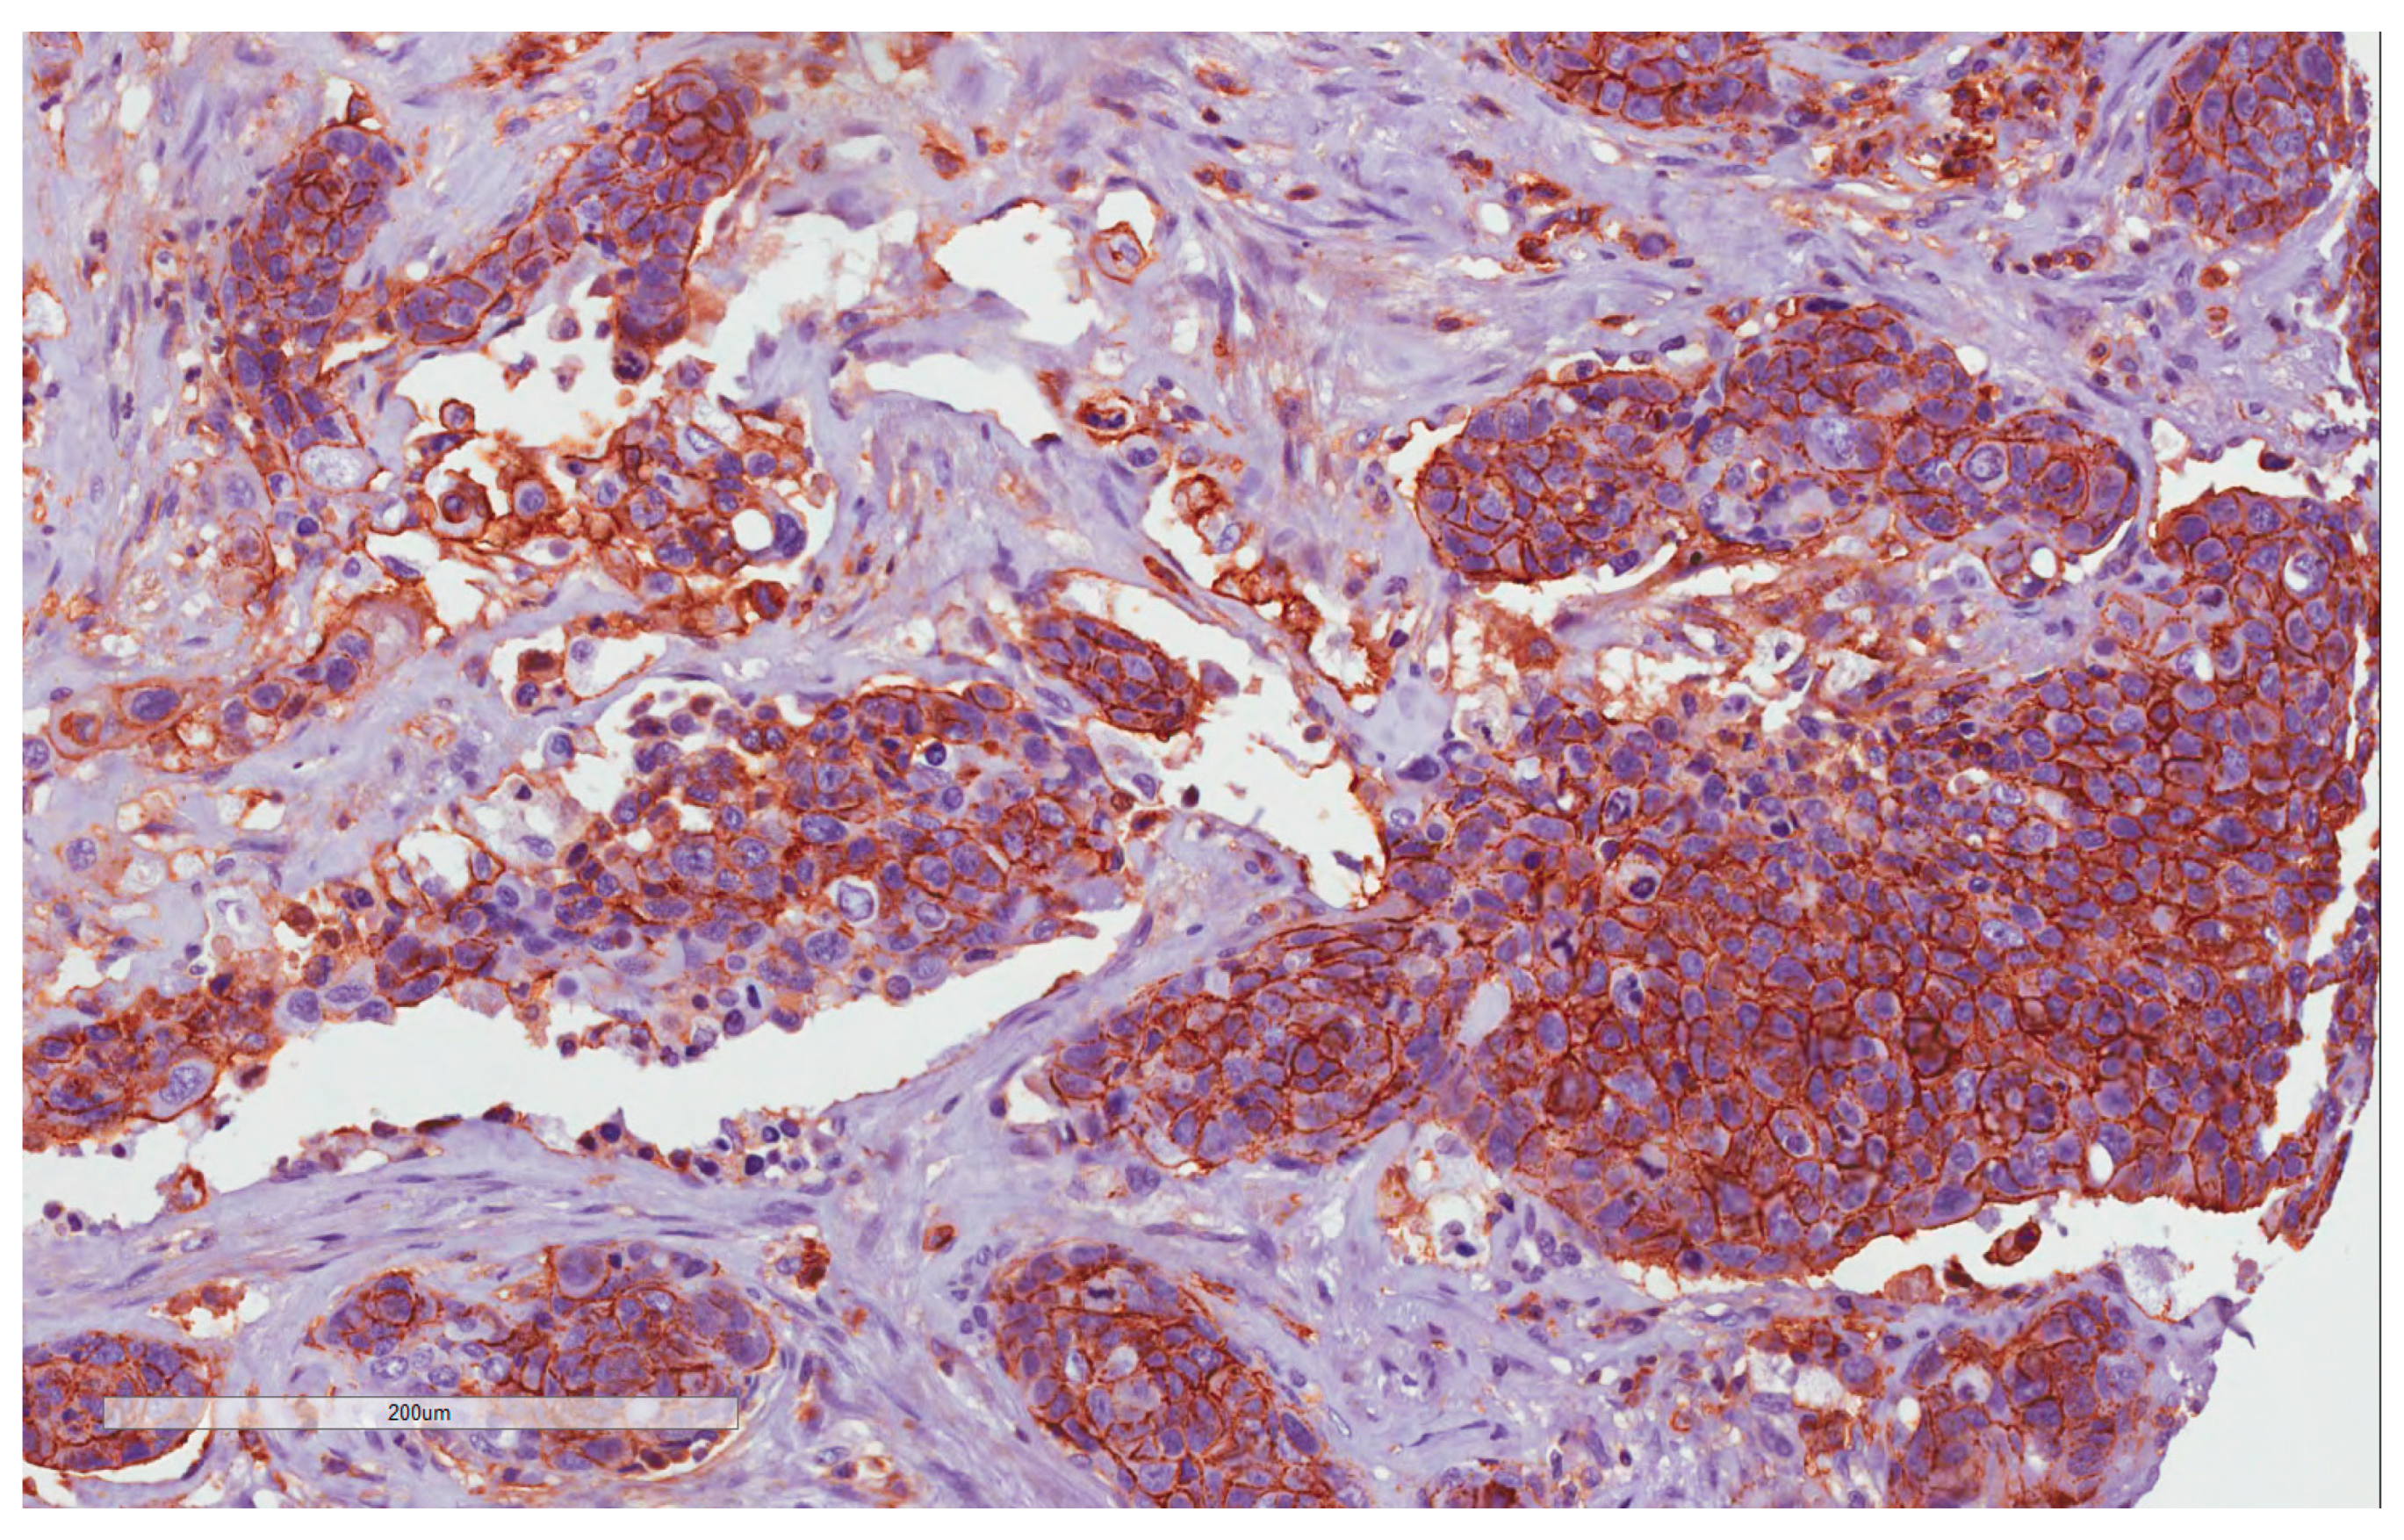

4.2. CD44 Expression

4.3. PDL1 Expression

4.4. ATG7 Expression